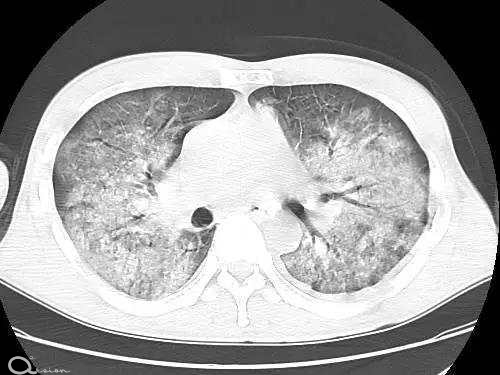

新冠中的白肺究竟是什么 它和肺炎、肺纤维化有什么区别

关于新冠感染后进展为“白肺”的话题频登热搜,“肺炎”“白肺”“肺纤维化”等话题引发网友关注和热议。这三种症状到底有何区别? 本站综…

白肺

肺纤维化

肺炎

缺氧

新冠

咳嗽